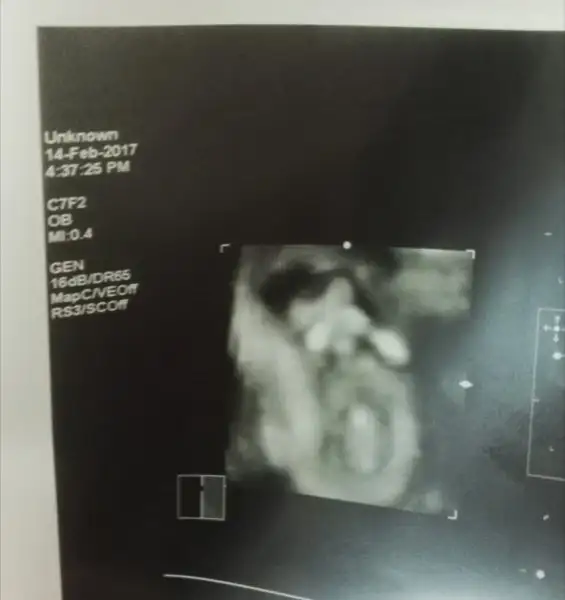

Çok şükür Burda böyle resimler böyle güzel cümlelerde duyuyoruz artık.. rabbim size bağışlasınEki Görüntüle 1953922

ellerini hep yüzüne kapatıyor benm nazlı kızımkontrole gittik gayet iyi teyzoşları. kesin olmamakla beraber kıza benzior dedi doktorumuz

Ama çok tatlı bu. Elleride büyümşde yüzünü kapatırmış. Maşallah minnoşa.Eki Görüntüle 1953922

Oy bu kesin kız çok utangaç :) mşlh rabbim bağışlasın :)Eki Görüntüle 1953922